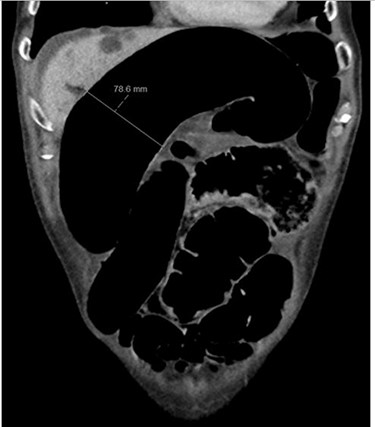

Blood tests on admission were unremarkable, with normal electrolytes levels and lactate. A plain abdominal film showed a typical appearance of caecal volvulus, with an inverted ‘comma sign’ (Fig. 4). A CT scan of the abdomen and pelvis with intravenous contrast was reported as sigmoid volvulus with the involved loops sitting predominantly in the right upper quadrant immediately inferior to the liver (Fig. 5).

Case two: a coronal slice of a CT scan of the abdomen and pelvis with intravenous contrast showing dilated large bowel loops; the radiology report suggested sigmoid volvulus with a centrally lying caecum.

Case two: a plain abdominal film showing dilated large bowel and the ‘inverted comma’ sign associated with caecal volvulus.